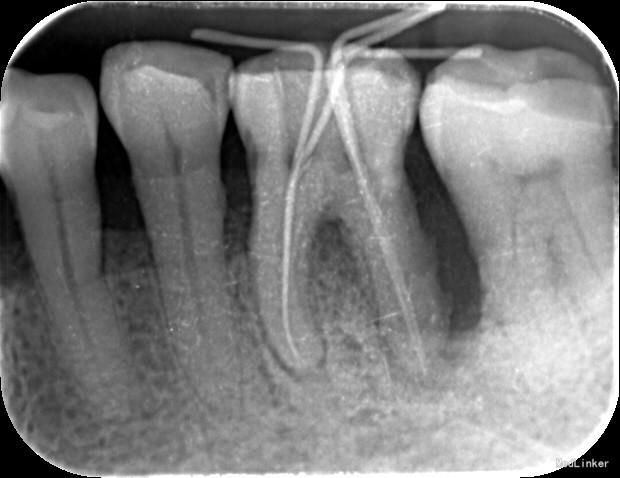

诊断:36牙周-牙髓联合病变 治疗计划:1、36牙周基础治疗 2、36根管治疗 治疗:1. 36碧兰麻局麻下牙合面开髓,暴露髓腔,降牙合,探及MB、ML、DB、DL四个根管口,MB、ML根管内大量血性渗出,DB、DL根管内少量脓性渗出,3%过氧化氢和0.9%生理盐水冲洗,隔湿,干燥,MB、ML根管口置非砷慢失活剂,DB、DL根管口置CP棉球,氧化锌水门汀暂封。 36龈下刮治,根面平整,3%过氧化氢和0.9%生理盐水冲洗,上碘甘油,嘱勿用患牙咬物。 2.主诉:左下后牙上次治疗后疼痛缓解 检查:36暂封物在,叩痛(—),牙体无松动,牙龈无明显红肿。 处置:36去除暂封物,拔残髓,10号C锉疏通根管,干燥根管,电测工作长度均为20mm。EDTA下,常规预备至35#,3%过氧化氢和0.9%生理盐水冲洗+超声荡洗根管交替进行。隔湿,干燥根管,封CP棉球, 氧化锌水门汀暂封。嘱勿用患牙咬物。 3.主诉:左下后牙上次治疗后无不适。 检查:36暂封物在,叩痛(—),牙体无松动,牙龈无明显红肿。 处置:36去除暂封物,取出棉球,生理盐水冲洗并干燥根管,复测工作长度同前。进口根充糊剂+牙胶尖冷侧压根管充填,氧化锌水门汀暂封。术后拍片示:36根充恰填。嘱勿用患牙咬物。